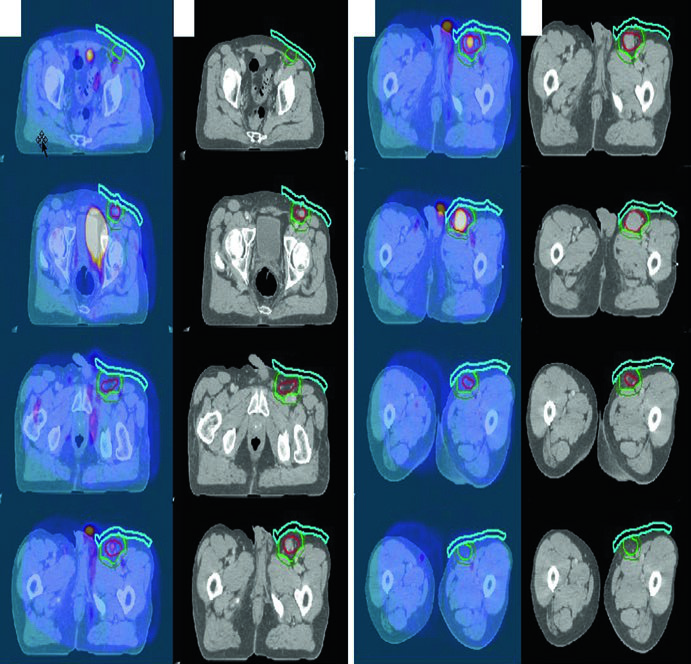

Follicular Lymphoma of the Groin

ISRT delineation for stage IA follicular lymphoma of the left inguinal/femoral region showing GTV in red, CTV in light green, and PTV in dark green with bolus

Figure 31.5 — Inguinal follicular lymphoma IA: GTV (red), CTV (light green), and PTV (dark green) with bolus. Source: Target Volume Delineation and Field Setup, 2nd Edition

A 70-year-old man with stage IA grade I/II follicular lymphoma of the left inguinal/femoral region was treated with definitive RT alone. Diagnostic PET was fused to the simulation CT. Bolus was used to increase superficial dose and improve dose coverage — a detail often overlooked for subcutaneous inguinal lesions.

Inguinal and Pelvic Lymphoma

Patients should be simulated in the frog-leg position to separate the leg from external genitalia and flatten inguinal skin folds, minimizing potential skin reactions. Shield the testicles with a clamshell in men and recommend sperm banking. For reproductive-age women, consider ovarian position. Modern techniques including 3DCRT and IMRT are recommended, with bolus added when needed for superficial dose.